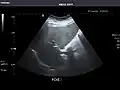

Right kidney -

Kidneys: Right and left kidneys measure 11.5 cm and 12 cm in length respectively. No hydronephrosis. Small left lower pole kidney cyst.